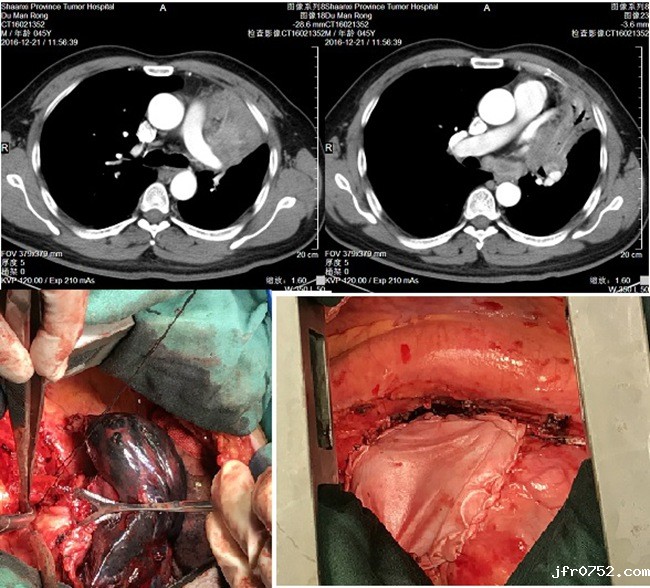

患者杜某,男性,45岁,因“咳嗽2月”慕名找到了我院胸外科主任雷光焰教授,入院完善各项检查后,确诊为左肺上叶鳞癌(中央型,分期cT4N2M0)。雷教授分析病情后认为:患者年轻,肺功能良好,左肺上叶病变范围大,与左肺动脉及左上肺静脉关系密切,但无远处转移,仍有手术完全切除可能,建议行术前新辅助化疗,以期提高手术切除率。但经过两周期的新辅助治疗后,患者左肺上叶病变未见明显缩小,手术难度依然很大。

鉴于患者及家属强烈的手术意愿,经全科术前讨论,与患者家属充分沟通后,于2016年12月27日在雷主任带领的胸外二病区治疗团队为这位年轻的患者施行了左全肺扩大切除+心包修补术。手术中先行清扫了肺门及隆突下多枚肿大融合淋巴结,单个直径达3cm,才使肺动脉干便于显露,由于病变包绕左上肺静脉,与心包融合,切开心包,经心包内游离左肺上叶静脉,紧贴心房离断缝合,整块切除肿瘤,心包缺损范围达10×8cm,以补片修补心包。手术过程顺利,术后10天康复出院。